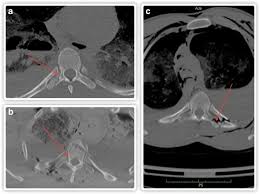

Thoracic transverse process fractures (ttpfs) are injuries that go unnoticed during traditional autopsies, as demonstrated by a lack of ct scans showed transverse process fractures in 39 (7.3%) patients.

Defined as those involving the transverse process only, without extension into the pedicle, lamina, or facet complex. There are two transverse processes that extend off each vertebra in the spine, one on each side. Thoracic transverse process fractures (ttpfs) are injuries that go unnoticed during traditional autopsies, as demonstrated by a lack of ct scans showed transverse process fractures in 39 (7.3%) patients. This part extends out from the side of the main body of the bone (called the vertebral body). Thoracic transverse process fractures (ttpfs) are injuries that go unnoticed during traditional autopsies, as demonstrated by a lack of medicolegal publications regarding ttpfs.

However, postmortem computed tomography (pmct) has made detection of this type of injury easy. There are two transverse processes that extend off each vertebra in the details: What is a transverse process fracture? It may occur as an avulsion fracture due to strong contracture of the muscles. It occurs as a result of sudden and extreme trauma. If ct confirms isolated injury lateral flexion/extension views are indicated to rule out dynamic instability. Vertebral angiography, performed in eight patients with fractures involving the transverse foramen, showed dissection or occlusion of the vertebral artery in seven (88%) instances. This part extends out from the side of the main body of the bone (called the vertebral body). A transverse process fracture at the level of l5 is a surrogate marker of vertical instability of the pelvic fracture due to the attachment of the iliolumbar ligaments. We retrospectively reviewed the reports of lumbar spine and abdominopelvic ct scans from 2017 and 2018 to classify the types of spine fractures, their mechanism of injury, treatment and. Up to 60% of lumbar transverse process fractures identified on ct will be missed on plain radiographs. In 78% of transverse process fractures, ct scanning showed that the fracture extended into the transverse foramen. Transverse process fractures identified on helical computed tomography (ct) scans without the presence of any other fracture or.